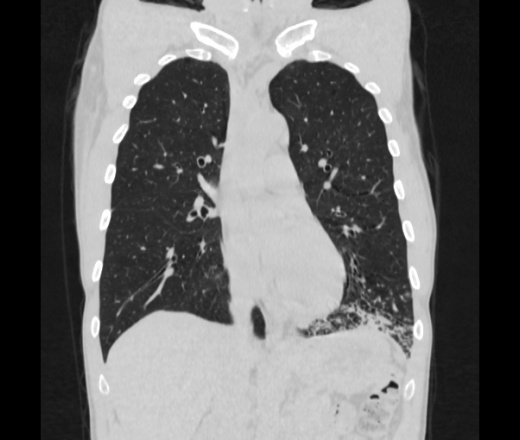

Мужчина пенсионного возраста. Цель назначения КТ ислючение зла в левом легком. Вижу тракционные бронхоэктазы с рубцовой эмфиземой по периферии, скорее всего БЭБ в стадии обострения. Дивертикулы трахеи. Выложил из за того что есть доля сомнения в отношении исключения зно3, немного смущают линии похожие на Керли.

Единственно, не сказал бы, что это тракционные бронхоэктазы, ну, и про линии Керли не вполне понял.

Ну да. Выразился не правильно. На фоне легочного рисунка усиленного линии похожие на септальные, не знаю как называются, при интерстиц.отеке похожие

На мой взгляд, это не главное, указал бы в описании - локально утолщен междольковый интерстиций, и всё